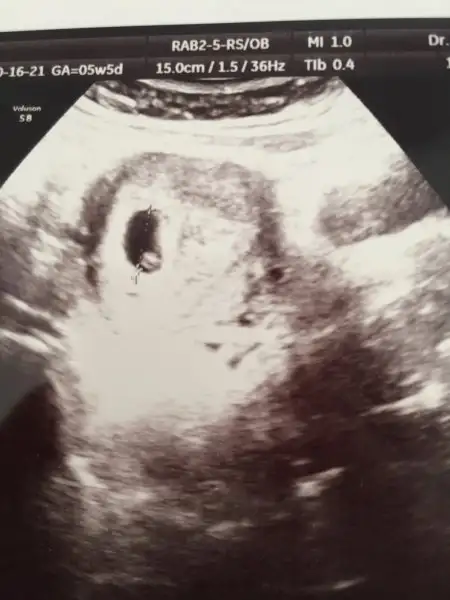

Kızlar merhaba doktorum kontrolde henüz bebeği göremiyoruz dedi ama kesenin içimdeki top bebek değil mi ? :))

Onu hiç bilmiyordum canım bende bebek sandım çok teşekkür ederim cevap için :)Yolk kesesi o oluyor herhalde canım yüzük gibi diyorlar ya.

Pazartesi özel e gittim kalp atışını duyduk çok şükür. Yeri çok güzel kalp atışı güçlü şimdilik bir sıkıntı yok dedi .6+6 dedi sata göre 3 gün geri . Muhtemel doğum tarihi 7 haziran dedi . Ben şuan yumurta peynir yoğurt falan yiyemedigim için muhallebi puding sütlaç ye azar azar dedi . 3 aydan sonra iştahın açılır zaten dedi . Ilişki için sorun yok dedi . D vitamini için 3 ay dan sonra dedi vs.. :) kan tahlili istedi bir sürü ama özel ceo yaktığı için devlete gidicem 2 hafta içind e işte .